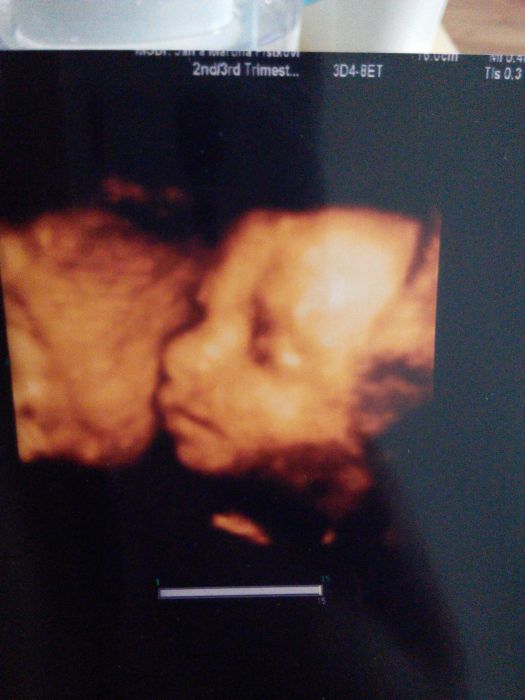

[898769] Krasny miminko! Ja bych toho naseho taky chtela videt, ale tady se za extra utz plati docela dost penez a za 3d/4d strasne moc.